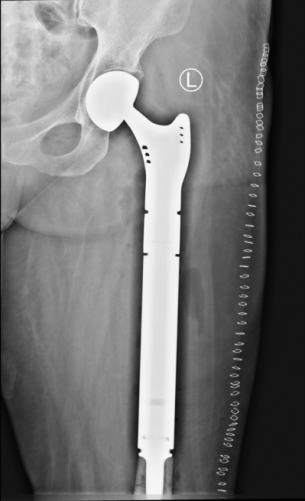

第一例患者女性,48岁,因“左大腿疼痛2月余,疼痛突然加重伴肿胀、畸形、活动障碍5天”入院。查体见痛苦病容,左大腿上端明显肿胀,呈屈曲、外旋、短缩畸形,左大腿中上段压痛明显,皮温升高,可触及骨擦感,左下肢活动障碍。初步诊断为左股骨病理性骨折。左股骨X线提示:左侧股骨近端虫蚀样骨质破坏并骨折,局部软组织密度改变。CT提示:左侧股骨上端广泛虫蚀状骨质破坏,中上段为著,周围软组织肿胀,考虑左侧股骨恶性骨肿瘤并病理性骨折。全身骨显像:左侧股骨中上段代谢异常增高伴软组织肿块,结合MRI考虑恶性骨肿瘤继发病理性骨折。后行穿刺活检,病理提示:符合转移性肺腺癌;(左侧远端髓腔肿物)见腺癌组织。由于患者非常痛苦,后并发下肢静脉血栓,其家属强烈要求手术,经我院医护对其全身严格评估并妥善处理下肢静脉血栓后,术前多学科讨论认为符合手术适应症,遂顺利行瘤段切除,人工假体置换重建术,髋关节囊及股骨上端重要肌肉附着点均使用laser韧带重建,历时3小时余。术后患者剧痛、烦躁、失眠等症状消失,活动明显增加,护理方便,医患双方对疗效非常满意,为后续治疗创造了有利条件。

术后X片图